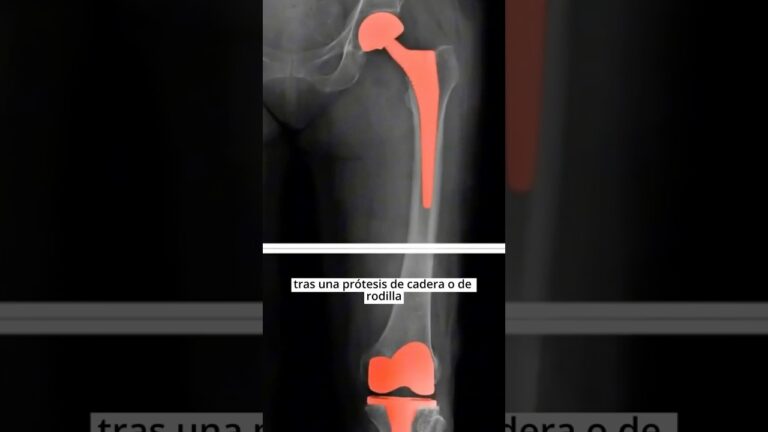

• con dos protesis de cadera se puede trabajar

¿Se Puede Trabajar con Dos Prótesis de Cadera? Guía Completa y Consejos Expertos

¿Alguna vez te has preguntado si es posible retomar tu actividad laboral después de recibir dos prótesis de…